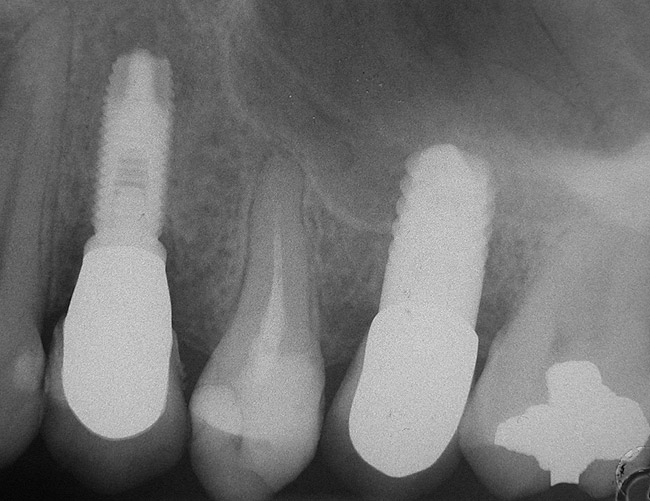

A 45-year-old female was referred for implant placement and prosthetic treatment in the area of tooth No. 24. The tooth had been extracted 4 years prior; the patient did not wear any denture thereafter. The radiograph revealed adequate bone height and a 5-mm to 6-mm ridge at the crest (Figure 2). It was decided to place a 11.5 mm in length, 3.75 mm in diameter Tapered Screw-Vent® implant (Zimmer Dental, www.zimmerdental.com) using the alveolar remodeling technique in the area of tooth No. 24.

At the time of surgery, local infiltrative anesthesia was administered (lidocaine 2% with epinephrine, 1:100,000). A full-thickness mucoperiosteal flap was raised. The initial osteotomy was performed on midcrestal bone using a rose-headed bur. To prepare the osteotomy site for implant placement, sequential alternating osteotomes with variable conicity were used, drilling 2-mm shorter than the length of the implant to be placed (Figure 3A and Figure 3B). The implants presented initial primary stability (Figure 4), the cover screws were placed, and the implants were submerged for a healing period. The tissue was approximated, and the patient was instructed not to wear any denture or to place pressure on the healing site.

Figure 2  Preoperative view of the area around tooth No. 24. On the left, a previously placed implant abutment is visible.

Figure 2

Figure 4  Implant positioning; the radiograph taken 4 weeks after placement confirmed good primary stability.

Figure 4